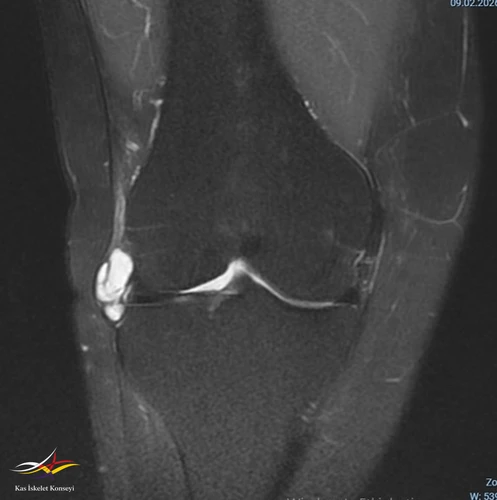

• Sağ diz MRG: Sağ diz ekleminde tibiofemoral ve patellofemoral eklem mesafeleri doğal olup, eklem yüzeyinde kartilaj yapı kalınlık ve sinyal intensiteleri tabiidir. Lateral menisküste longitudinal seyirli ve periferik uzanımlı rüptür ile lateral komşuluğunda LCL'yi deplase eden 22x32 mm boyutlu lobüle konturlu septalı parameniskal kist izlenmiştir. Medial menisküsün morfoloji ve sinyal intensite dağılımı doğal izlenmiş olup, patolojik sinyal intensite değişikliği saptanmamıştır. ACL, PCL'de hafif sprain mevcut olup, MCL, LCL tabiidir. Patellar ve quadriceps tendonların bütünlük ve sinyal intensiteleri tabiidir.